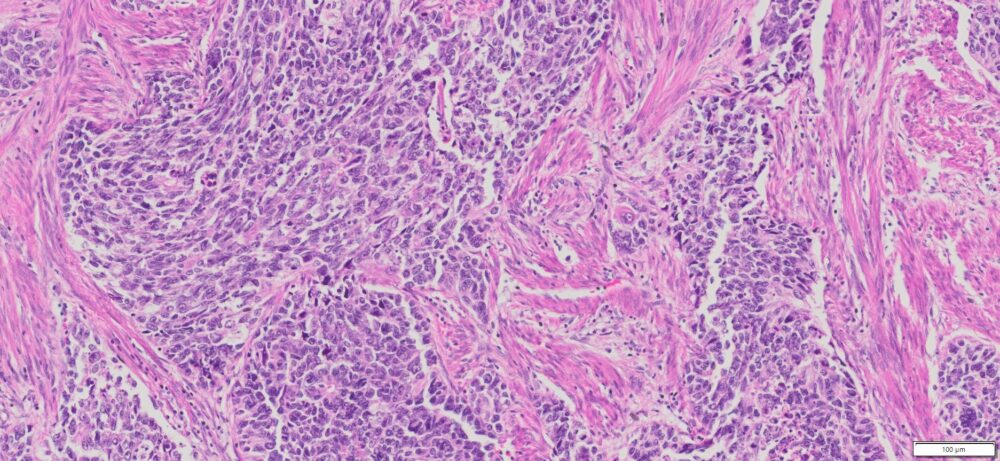

Description

| Organ& Tissue | Pathology Diagnosis | Gender/Age | % Tumor Area | Grade | TMN Stage | Biomarkers |

| Endometrial | Endometrial carcinosarcoma (malignant mixed Müllerian tumor) | Female/52 | 40% | NA | pT3apN1Mx | MLH1-2,MLH6 and PMS2: Intact nuclear expression |

More Images of H&E Stain and IHC